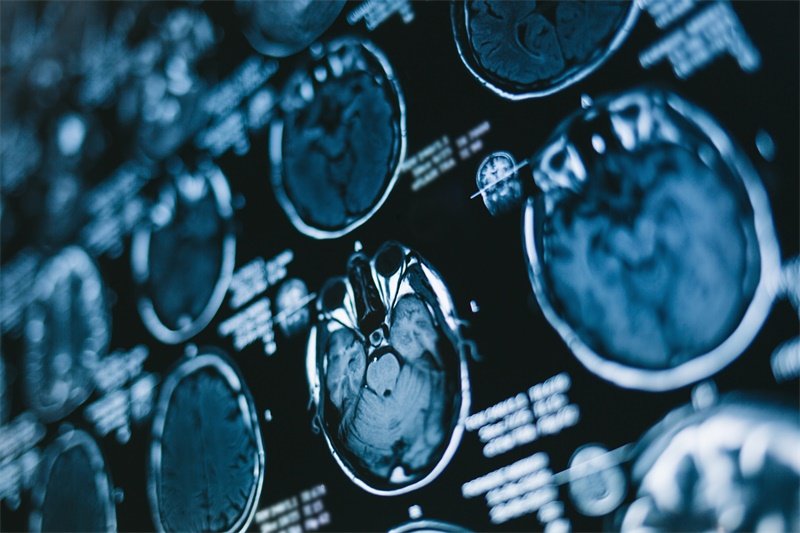

在诊断侧脑室脉络丛囊性占位时,专业的医疗团队通常会结合患者的病史、临床症状及影像学检查结果来做出综合判断。常用的影像学检查方法就是核磁共振成像(MRI)和计算机断层扫描(CT)。

MRI能够提供详细的脑部图像,对于识别侧脑室的结构和囊性占位非常有效。此外,CT扫描也可以用于快速评估,但在细节上可能不如MRI清晰。这些影像学检查能够帮助医生确定囊性占位的大小、位置及其与周围组织的关系。